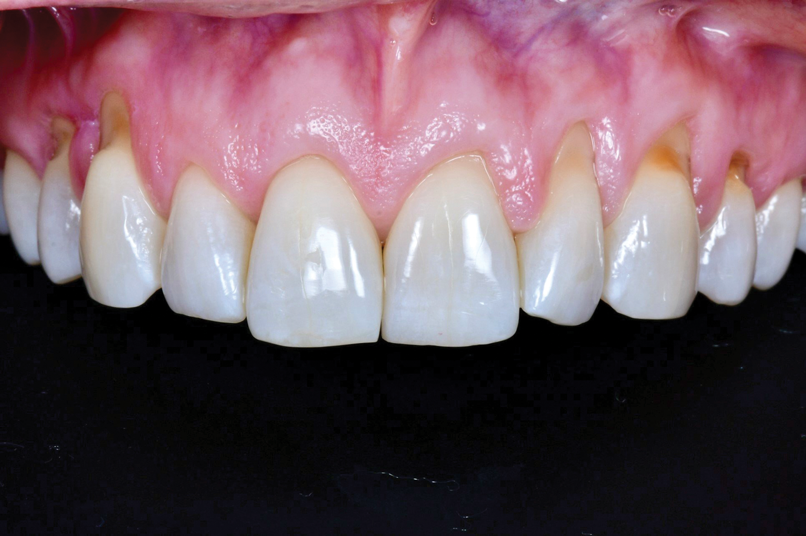

A female patient presented to the practice with generalized gingival recession in the maxilla that extended from tooth No. 4 to tooth No. 13 (her maxillary first premolars were missing). The recession was classified as Cairo RT1 for all affected teeth, and the root exposure ranged from 1 mm to 4 mm. As part of the examination, radiographs were acquired; however, no remarkable interproximal bone loss was observed (Figure 5). Teeth Nos. 4, 6, 10, 11, and 13 were the most severely affected, and NCCLs were present on the canines and premolars (Figure 6). More specifically, tooth No. 4 presented with 3 mm of recession and an NCCL; tooth No. 6 presented with 3 mm of recession and an NCCL; teeth Nos. 7 through 9 presented with 1 mm of recession and no NCCLs; tooth No. 10 presented with 4 mm of recession and an NCCL; tooth No. 11 presented with 4 mm of recession and an NCCL; and finally, tooth No. 13 presented with 3 mm of recession and an NCCL. All of the NCCLs demonstrated a Winter and Allen classification of NCL3. The patient's keratinized tissue was greater than 2 mm for all teeth, her periodontal phenotype was thick, and her midline frenum was prominent and inserted 5 mm apical to the tip of the papilla between teeth Nos. 8 and 9.

(6.) Preoperative retracted view of the generalized gingival recession in the maxilla extending from tooth No. 4 through tooth No. 13.

Figure 6

The patient's postoperative healing was uneventful. She reported light bruising; however, no bruising was observed at the suture removal appointment. She also indicated experiencing moderate pain but only during the first three days after surgery. By 12 weeks, nearly 100% root coverage was observed, and the quality of the tissue, which was thick, keratinized, pink, firm, and dense, remained stable. Inflammation was minimal, and the patient's oral hygiene was good. At the 1-year follow-up appointment, the observed results had been maintained and still demonstrated excellent esthetics (Figure 10).

(10.) Postoperative view at the 1-year follow-up appointment. Note how the final results were maintained.

Figure 10